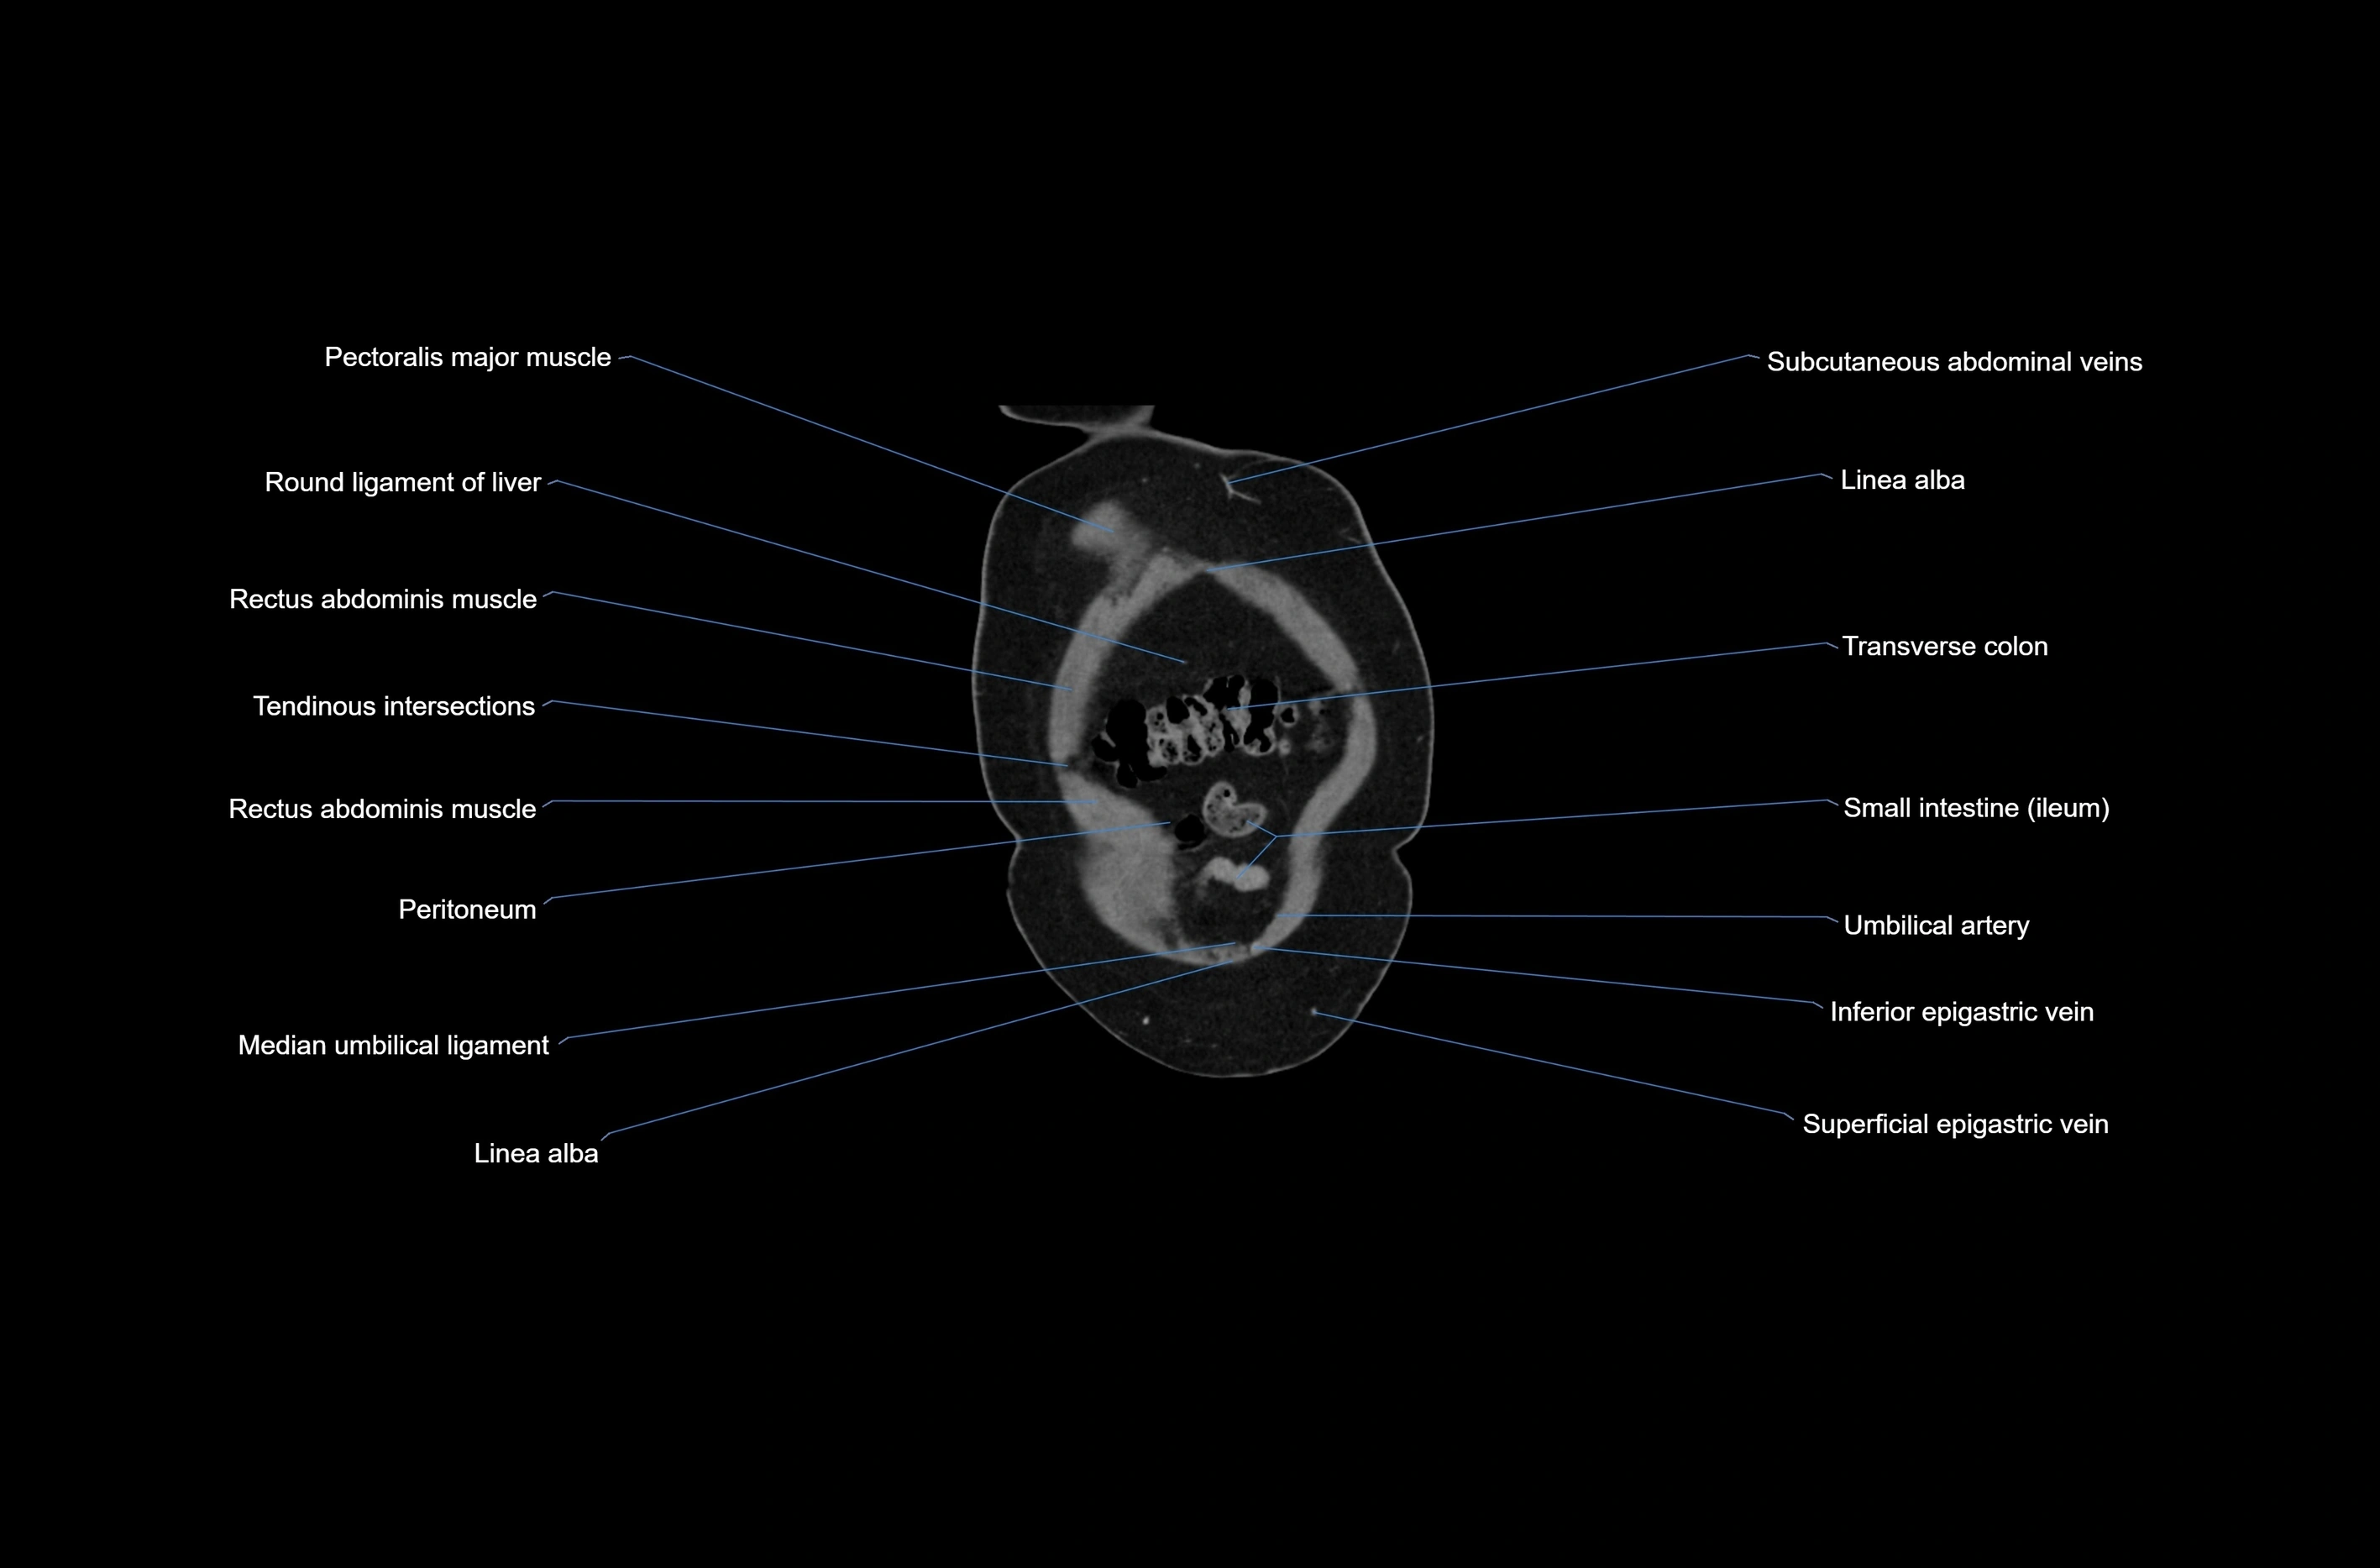

- Linea alba

- Median umbilical ligament

- Rectus abdominis muscle

- Umbilical artery